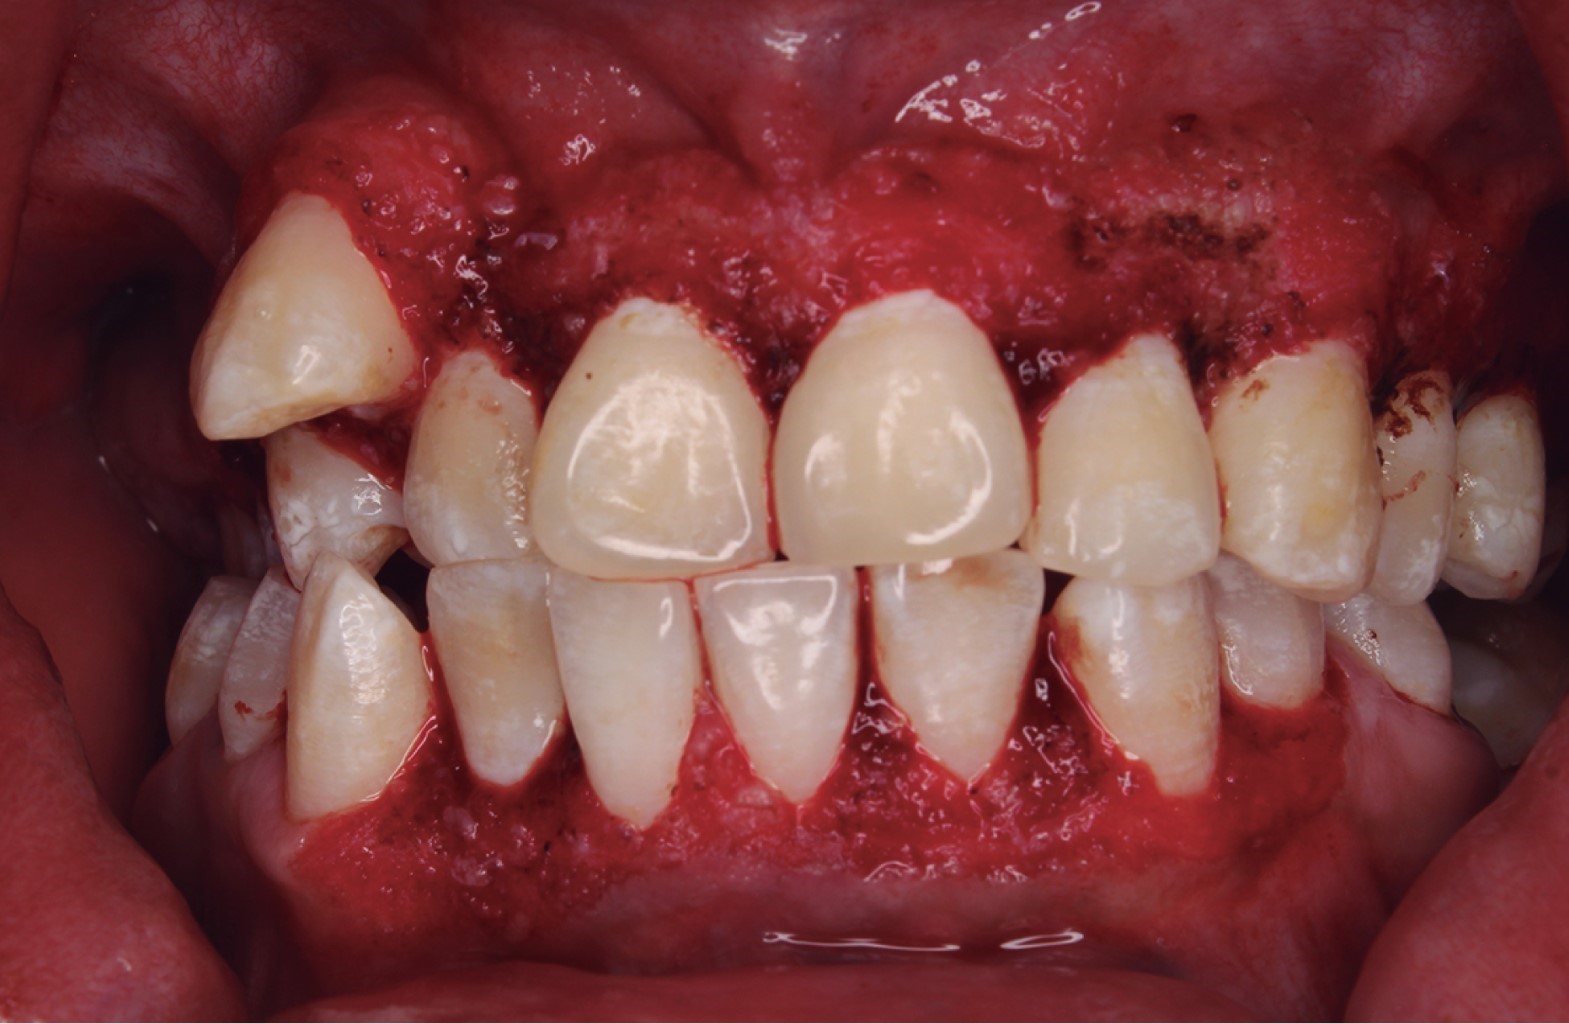

Se realizó la gingivectomía y gingivoplastia en ambos sextantes (Figura 3). Terminando el procedimiento quirúrgico se colocó una membrana de satín hemostático absorbible (Lides S-100) en la cara vestibular del sextante #2 (Figura 4). Se recetó amoxicilina de 500 mg cada ocho horas por siete días, ibuprofeno 600 mg cada ocho horas por cinco días, ketorolaco 10 mg cada ocho horas por cinco días, y enjuagues de clorhexidina al 12% con indicaciones al paciente y se le dieron citas de revisión (Figura 5).

Al colocar la membrana de celulosa oxidada regenerada (Lides S-100) se logró menor grado de inflamación y mayor protección en el sitio quirúrgico. El paciente no refiere dolor ni inconformidad postquirúrgica. A los 15 días de evolución se observa el tejido gingival un poco eritematoso ya epitelizado, se decide realizar una segunda profilaxis para retirar restos de placa dentobacteriana. Dos meses después del procedimiento quirúrgico, el paciente presenta conformidad con la estética, se observa el tejido completamente epitelizado y color rosa pálido, encontrándose leve acúmulo de placa en zona anterior, se le refuerza al paciente y a su tutora la técnica de cepillado. A los cinco meses de evolución se observa buena cicatrización; sin embargo, hay presencia de papilas con aumento breve de volumen y eritematosas relacionado al acúmulo de placa dental y al uso continuo de la fenitoína.

Figura 4